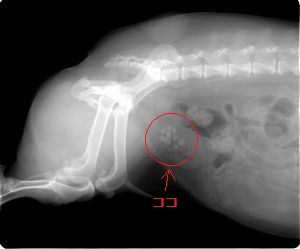

レントゲンで見た膀胱結石。

小さい結石が何個もあるのが分かります。